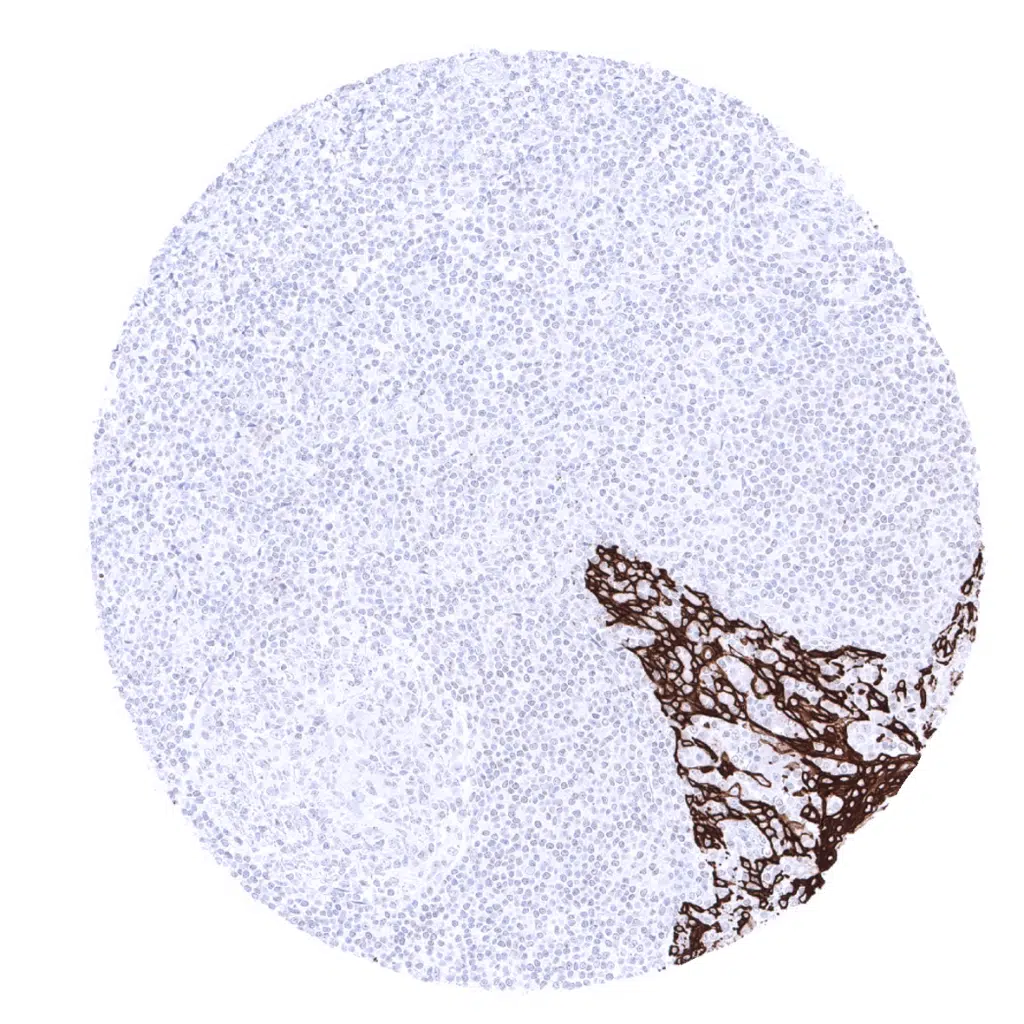

Lymph node